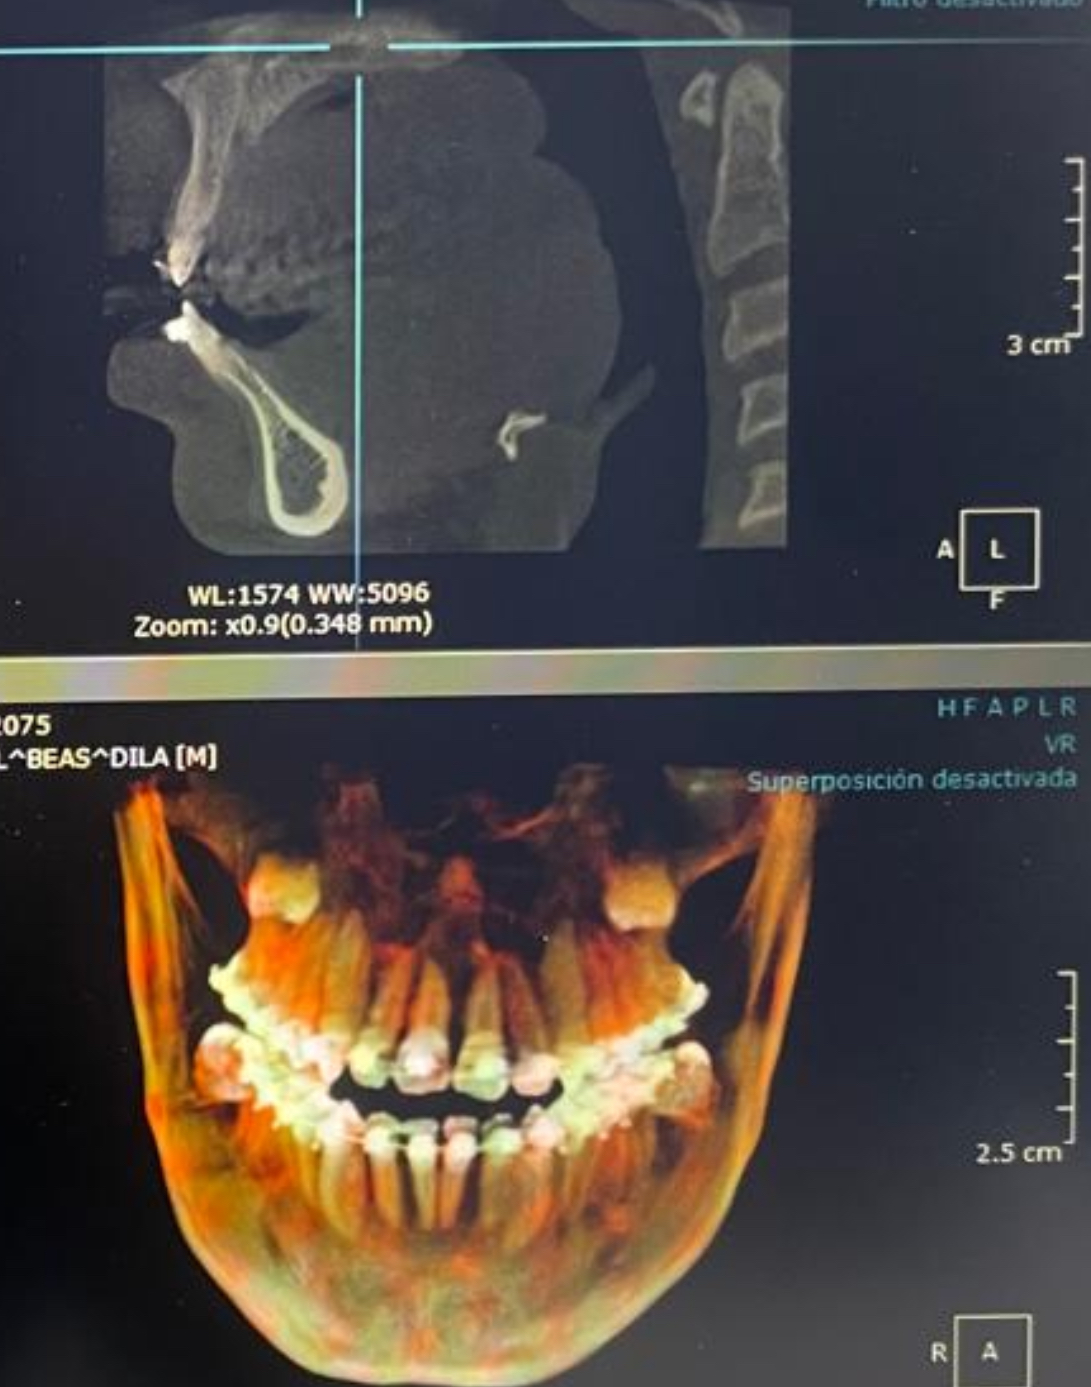

ltn-htn via double jaw surgery dowgrafting + ccw